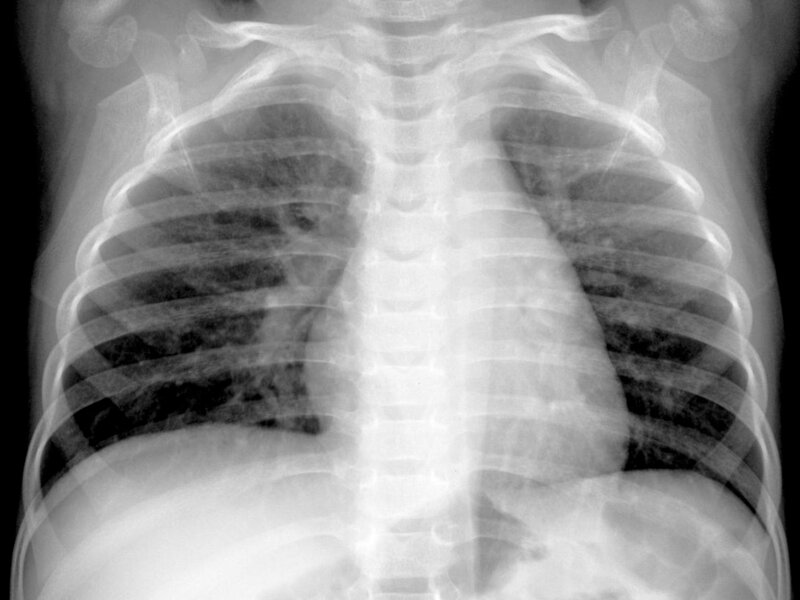

Can HMPV lead to pneumonia?

Respiratory infections are among the most common illnesses affecting both children and adults, and while many are mild, some can escalate into serious conditions. One virus that has gained increasing attention in recent years is human metapneumovirus (HMPV). Although it may sound unfamiliar compared to well-known viruses like influenza or RSV, HMPV is a significant…